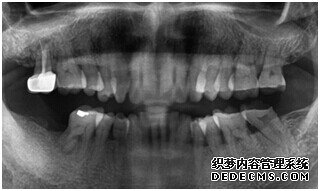

成功植入种植体后的效果图

种植体成功植入后的CT效果图

整个种植牙完成后的效果图